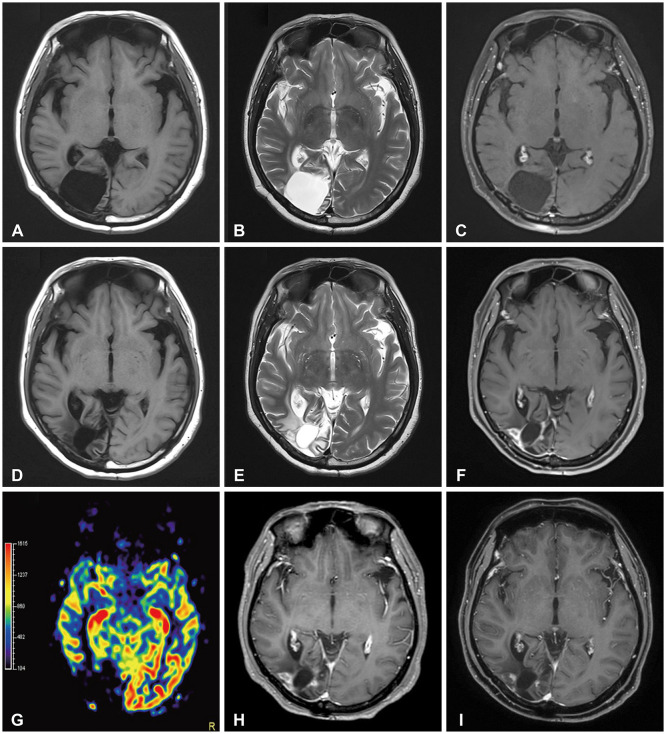

Delayed cerebral necrosis is a well-known complication of radiation therapy (RT). Because of its irreversible nature, it should be avoided if possible, but avoidance occurs at the expense of potentially compromised tumor control, despite the use of the modern advanced technique of conformal RT that minimizes radiation to normal brain tissue. Risk factors for radiation-induced cerebral necrosis include a higher dose per fraction, larger treatment volume, higher cumulative dose, and shorter time interval (for re-irradiation). The same principle can be applied to proton beam therapy (PBT) to avoid delayed cerebral necrosis. However, conversion of PBT radiation energy into conventional RT is still short of clinical support, compared to conventional RT. Herein, we describe two patients with excessively delayed cerebral necrosis after PBT, in whom follow-up MRI showed no RT-induced changes prior to 3 years after treatment. One patient developed radiation necrosis at 4 years after PBT to the resection cavity of an astroblastoma, and the other developed brainstem necrosis that became symptomatic 6 months after its first appearance on the 3-year follow-up brain MRI. We also discuss possible differences between radiation changes after PBT versus conventional RT.